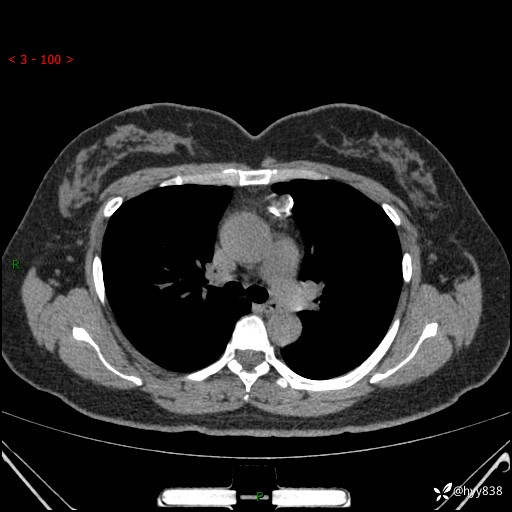

中年女性,检查发现纵隔占位3月余。圆圆的肿物,周围环绕一圈钙化---结果公布~

主诉:检查发现纵隔占位3月余。

现病史:患者于3月前体检行胸部CT检查发现纵隔占位,患者平素无明显咳嗽咳痰,无心慌、胸闷、胸痛、呼吸困难、低热、盗汗,无头痛、头晕,无腹痛、腹胀等不适。现患者欲求进一步治疗,遂来我院就诊,以“纵隔占位”收入我科。 患者自起病以来,精神可,睡眠可,饮食可,大小便正常,体重无明显改变。

胸部CT平扫+增强